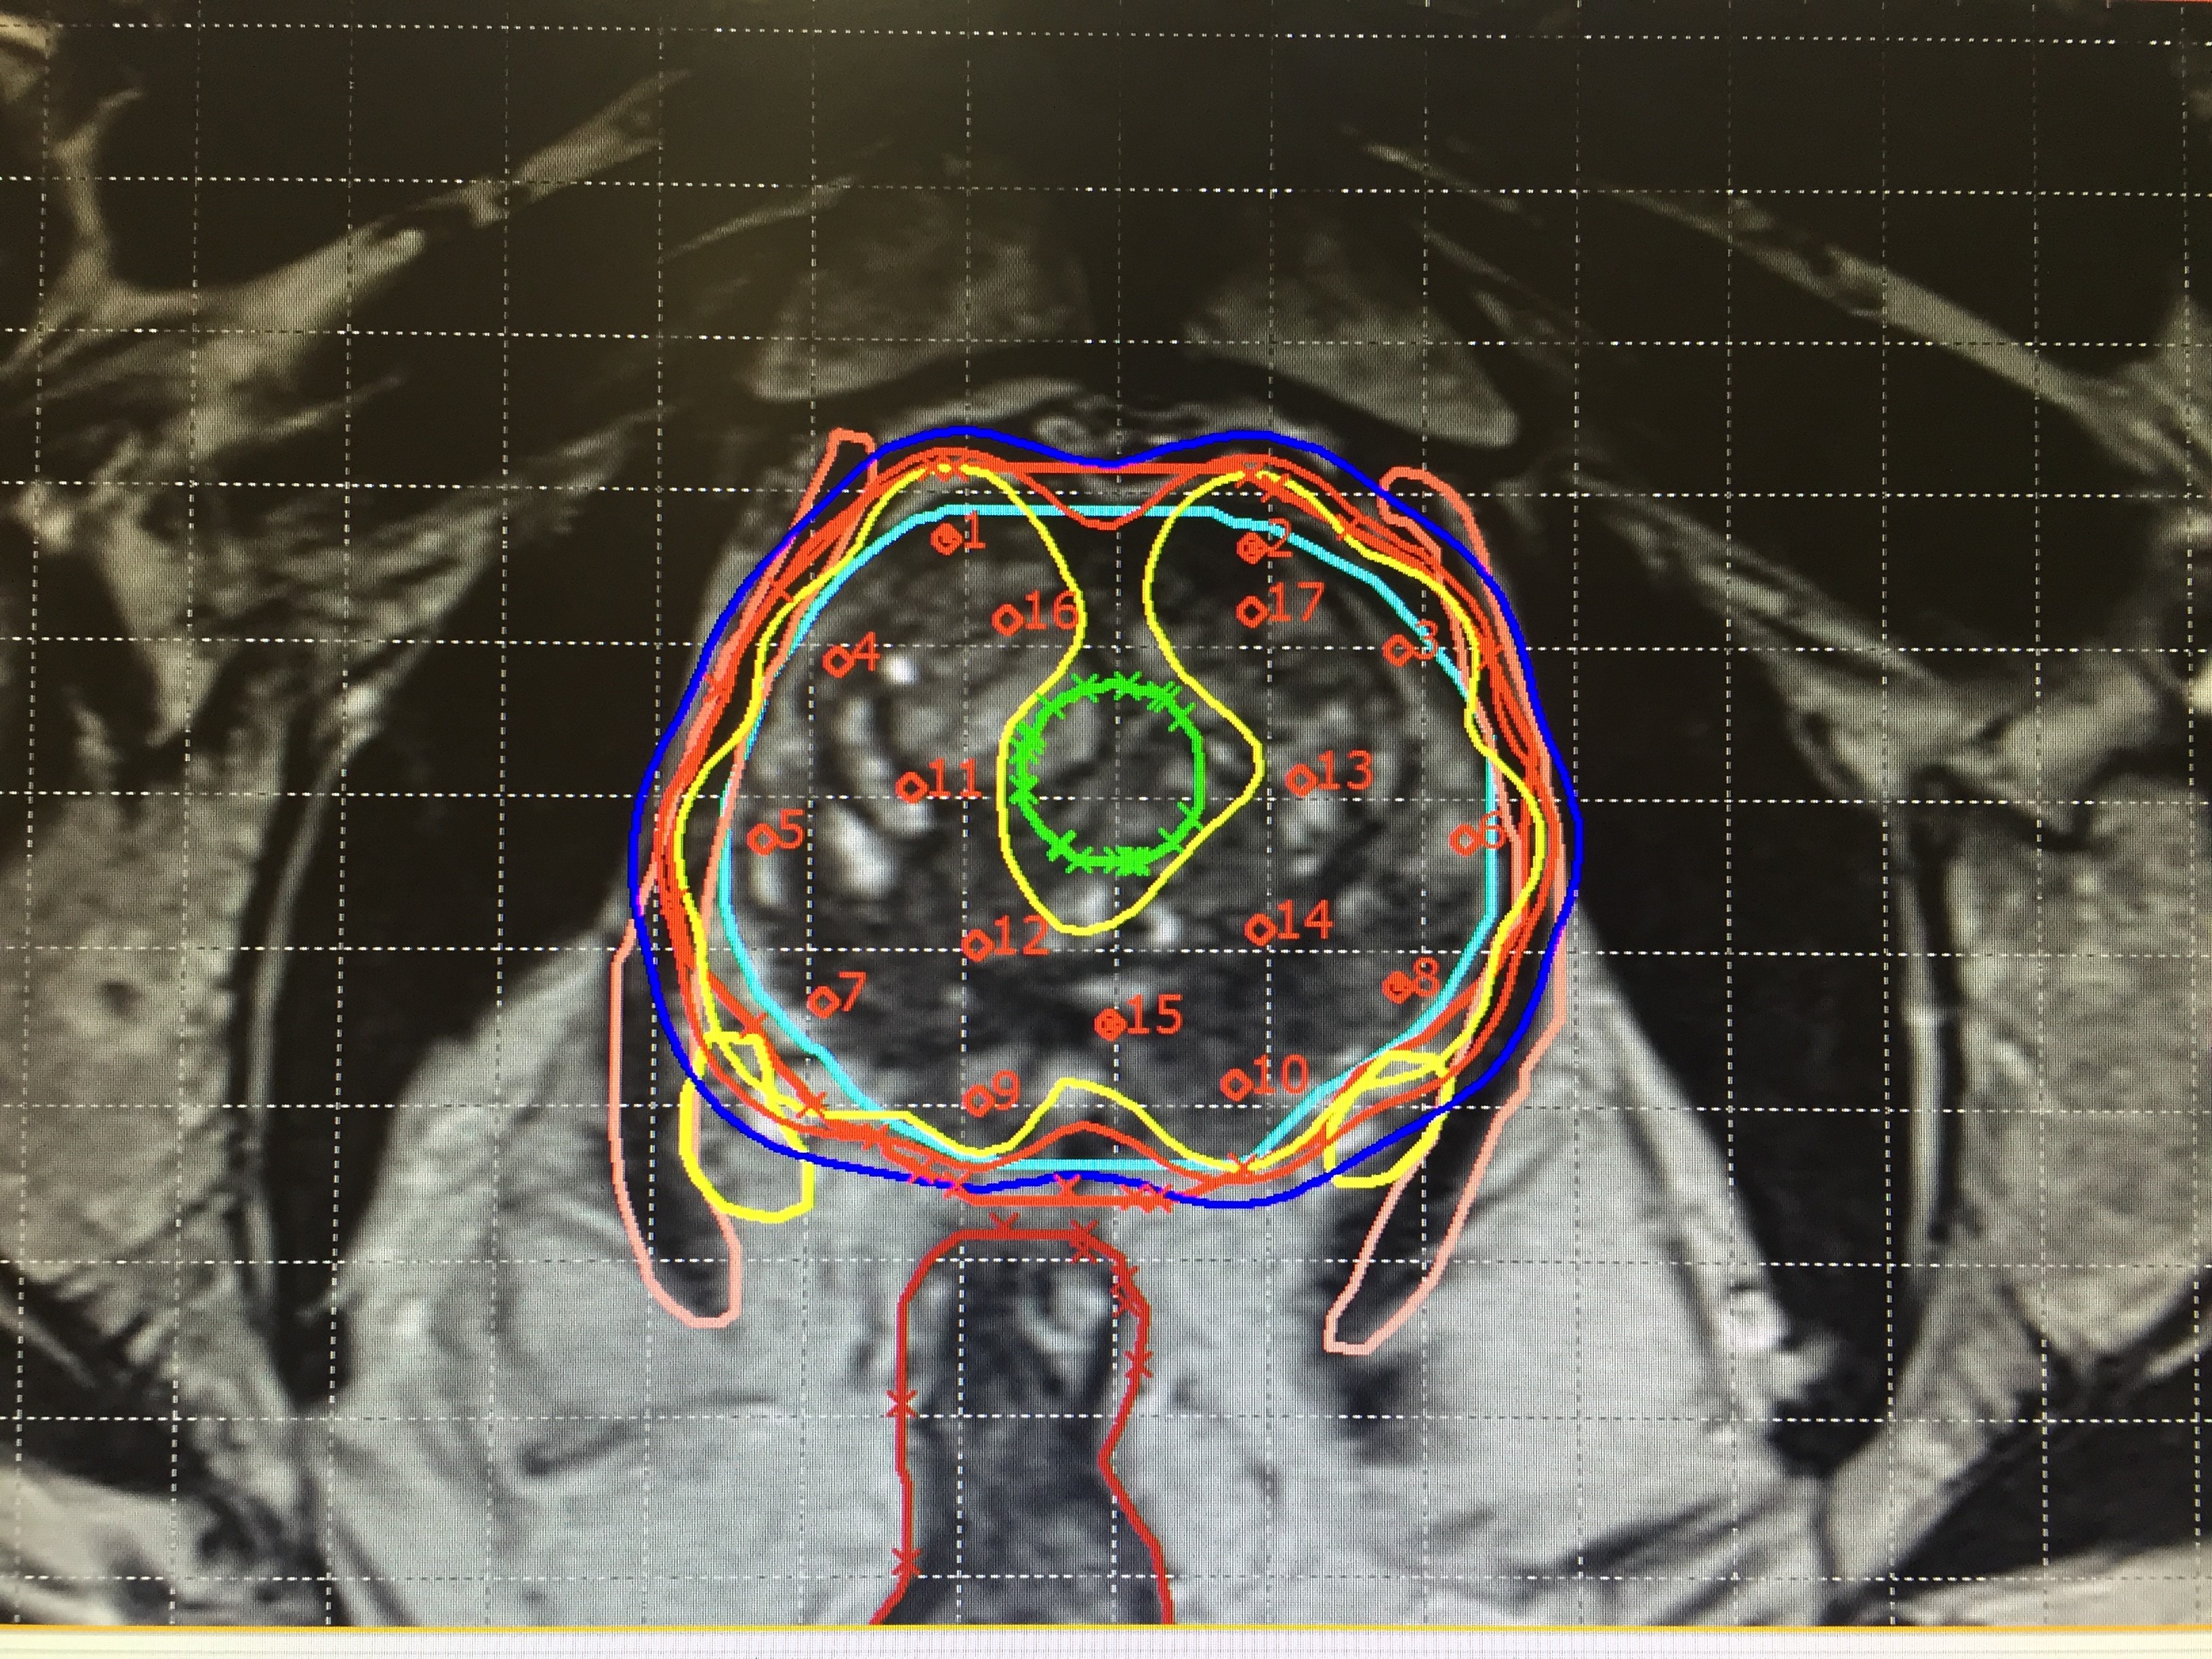

Detailed medical images help health professionals distinguish between tumours, healthy tissue and organs to ensure radiation sources are correctly targeted. (Photo: Auna Oncosalud)

IGBT is designed to maximize the radiation dose to kill cancer cells while minimizing the exposure of the surrounding healthy cells. It uses detailed 3D medical images to capture organ volume changes in order to tailor and optimize brachytherapy for patients’ needs. The images show the exact size and location of a tumour and relevant organs in order for the healthcare team to precisely plan and safely place radioactive sources directly next to or inside a tumour for treatment. This placement can either be temporary, using a removable applicator containing the sources, or permanent, using sources called seeds that remain indefinitely inside the body; over time, the seeds lose their radioactivity and become harmless.

However, placing the sources inside a patient’s body requires expertise in various disciplines, such as surgery, imaging and contouring, and treatment planning, explained Alfredo Polo Rubio, a radiation oncologist at the IAEA. “It is not a ‘one-size-fits-all’ procedure, since each patient’s body and each tumour is different, and brachytherapy is a kind of personalized treatment. Combining brachytherapy with imaging gives the healthcare team a clearer view of the tumour and the surrounding organs and facilitates the placement of the radiation sources, assessment of tumour response and more accurate adjustment of radiation doses.”